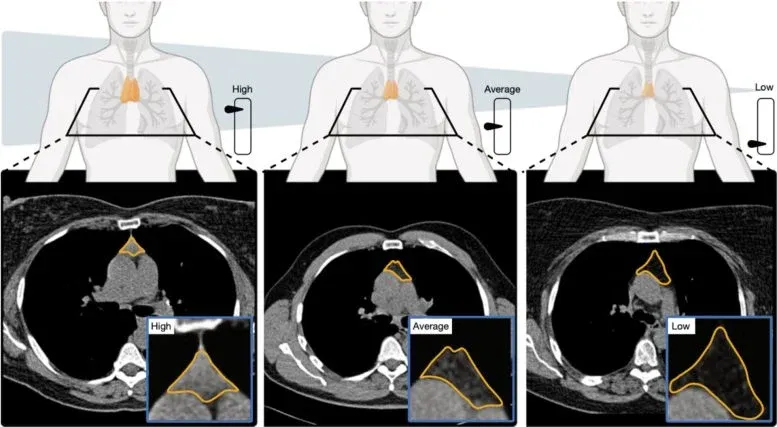

His team's first study crunched data from over 25,000 adults in a lung cancer screening program and another 2,500 from the Framingham Heart Study. They measured the thymus's size, structure, and makeup to create a "thymic health" score. The results? People with higher scores had a roughly 50% lower risk of death overall, a 63% lower risk of dying from heart disease, and a 36% lower risk of lung cancer. Let that satisfying number sink in.